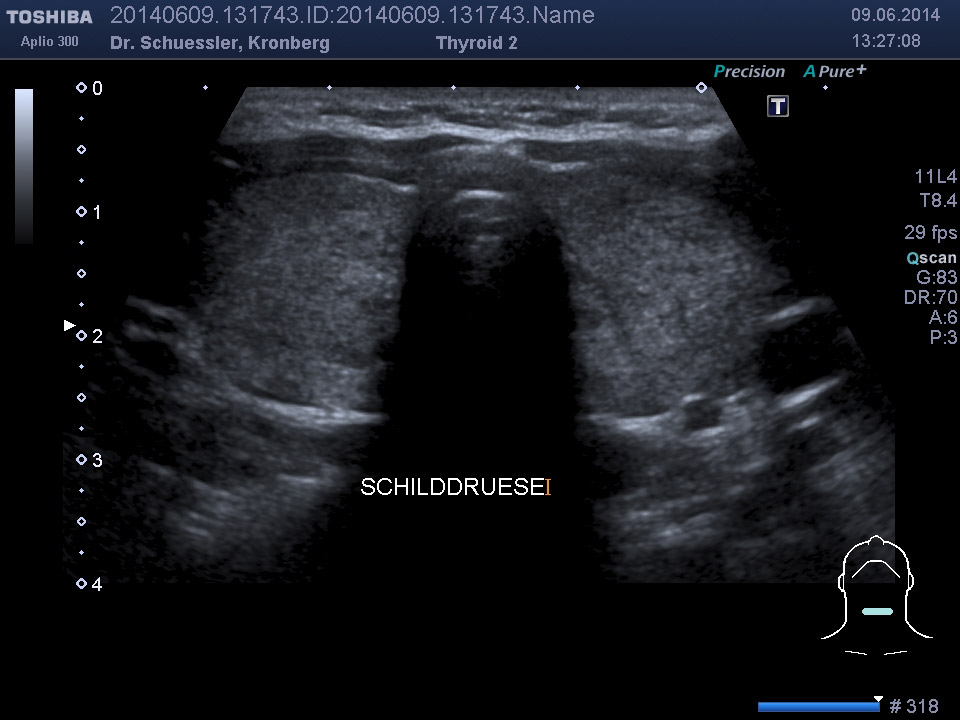

Farbkodierte Ultraschalluntersuchung der Schilddrüse

Mit dieser Untersuchung lassen sich die Schilddrüsengröße, ihre Struktur und auch Knoten, Zysten oder entzündliche Veränderungen sichtbar machen. Durch Hinzunahme der Farbkodierung lässt sich auch die Durchblutungssituation der Schilddrüse sichtbar machen.